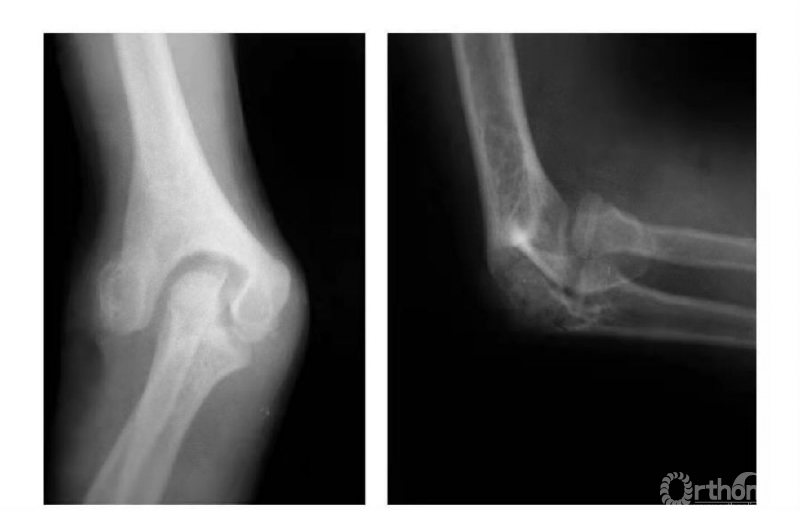

例4:肱骨内髁滑车骨折,且骨块内移,致骨骺因损伤而早闭,并形成肘内翻畸形(图7)。

图7

例5:肱骨内髁外侧壁骨骺因损伤而早闭,而内外侧骨骺继续生长致滑车沟变深,继而肱骨下端形成鱼尾状畸形(图8)。

图8